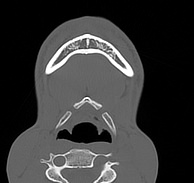

Лицевой череп состоит из крупных костей (верхняя и нижняя челюсти, лобные кости, скуловые кости) и сгруппированных вокруг них остальных мелких костей. При травмах лицевых костей часто наблюдается смещение мелких отломков, которые не видны при обычной рентгенографии. Мультиспиральная компьютерная томография позволяет детально изучить кости лицевого черепа, а также углубления, которые являются вместилищем для важных органов (глазницы, полость носа, ротовая полость).

Метод КТ основан на применении рентгеновского излучения и различной способности тканей поглощать рентгеновские лучи. Костные структуры обладают наибольшей плотностью по сравнению с другими тканями, поэтому в большей степени поглощают рентгеновские лучи и лучше всего визуализируются при данном исследовании.

КТ костей лица является наиболее информативным методом диагностики травм лицевого черепа, посттравматических деформаций, аномалий развития, инородных предметов в носовой полости и околоносовых пазухах. Кроме того, мультиспиральная КТ применяется при воспалительных заболеваниях ЛОР-органов, а также для выявления опухолевых образований доброкачественного и злокачественного характера.

Детальные изображения костей лицевого черепа получаются за счет вращения трубки томографа с излучателями рентгеновских лучей вокруг объекта исследования. В аппаратах увеличено количество сверхчувствительных детекторов, позволяющих производить множество послойных снимков с толщиной среза от 0,5 мм, которые затем преобразуются в трехмерные пространственные модели черепа. Такие инновационные возможности аппаратов обеспечивают проведение точной и достоверной диагностики.